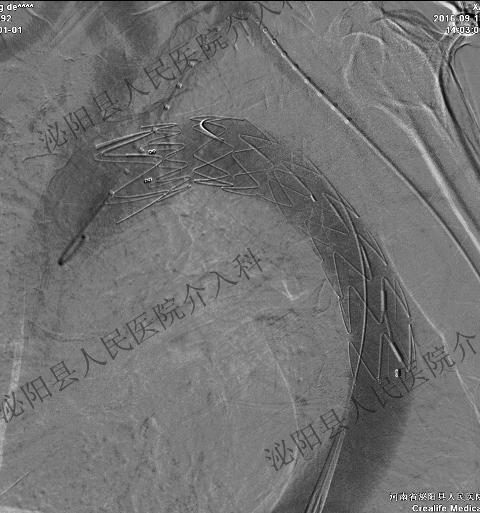

主动夹层,经皮覆膜支架腔内隔绝术:

胸主动脉瘤,经皮覆膜支架腔内隔绝术: